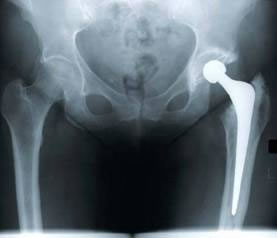

• Cirurgia: As principais técnicas cirúrgicas são as artroplastias (próteses) ou artroscopias para limpeza da articulação.